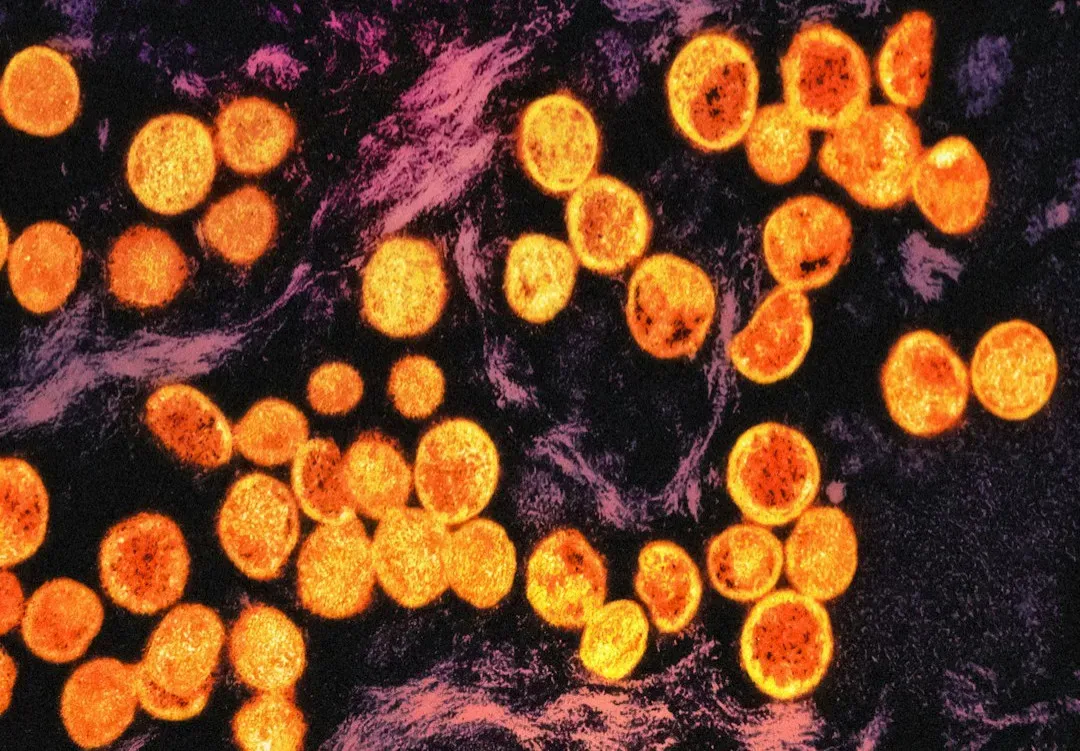

Cellular Reprogramming: Turning Back The Clock Inside Our Cells

One of the most dramatic ideas in longevity science is cellular reprogramming: taking old cells and nudging them back toward a younger state. Scientists discovered that by switching on a handful of key genes in adult cells, they could reset them to something close to embryonic stem cells, wiping away many signs of age. That’s powerful but dangerous – turn the clock back too far and you risk cancer or losing the cell’s identity entirely. The new frontier is “partial reprogramming,” where those youth-inducing genes are switched on just long enough to rejuvenate cells without making them forget what they are.

In mice, this partial reset has made tissues like muscles and nerves look and act younger, and in some experiments it has even extended lifespan. Imagine being able to refresh worn-out heart cells after a heart attack, or dial down aging signals in the brain to protect against dementia. It’s still early, and nobody wants to unleash something that could trigger tumors years later, but the concept is intoxicating: instead of simply slowing aging, you might be able to reverse parts of it. To me, this is where the line between medicine and something closer to time travel starts to blur.